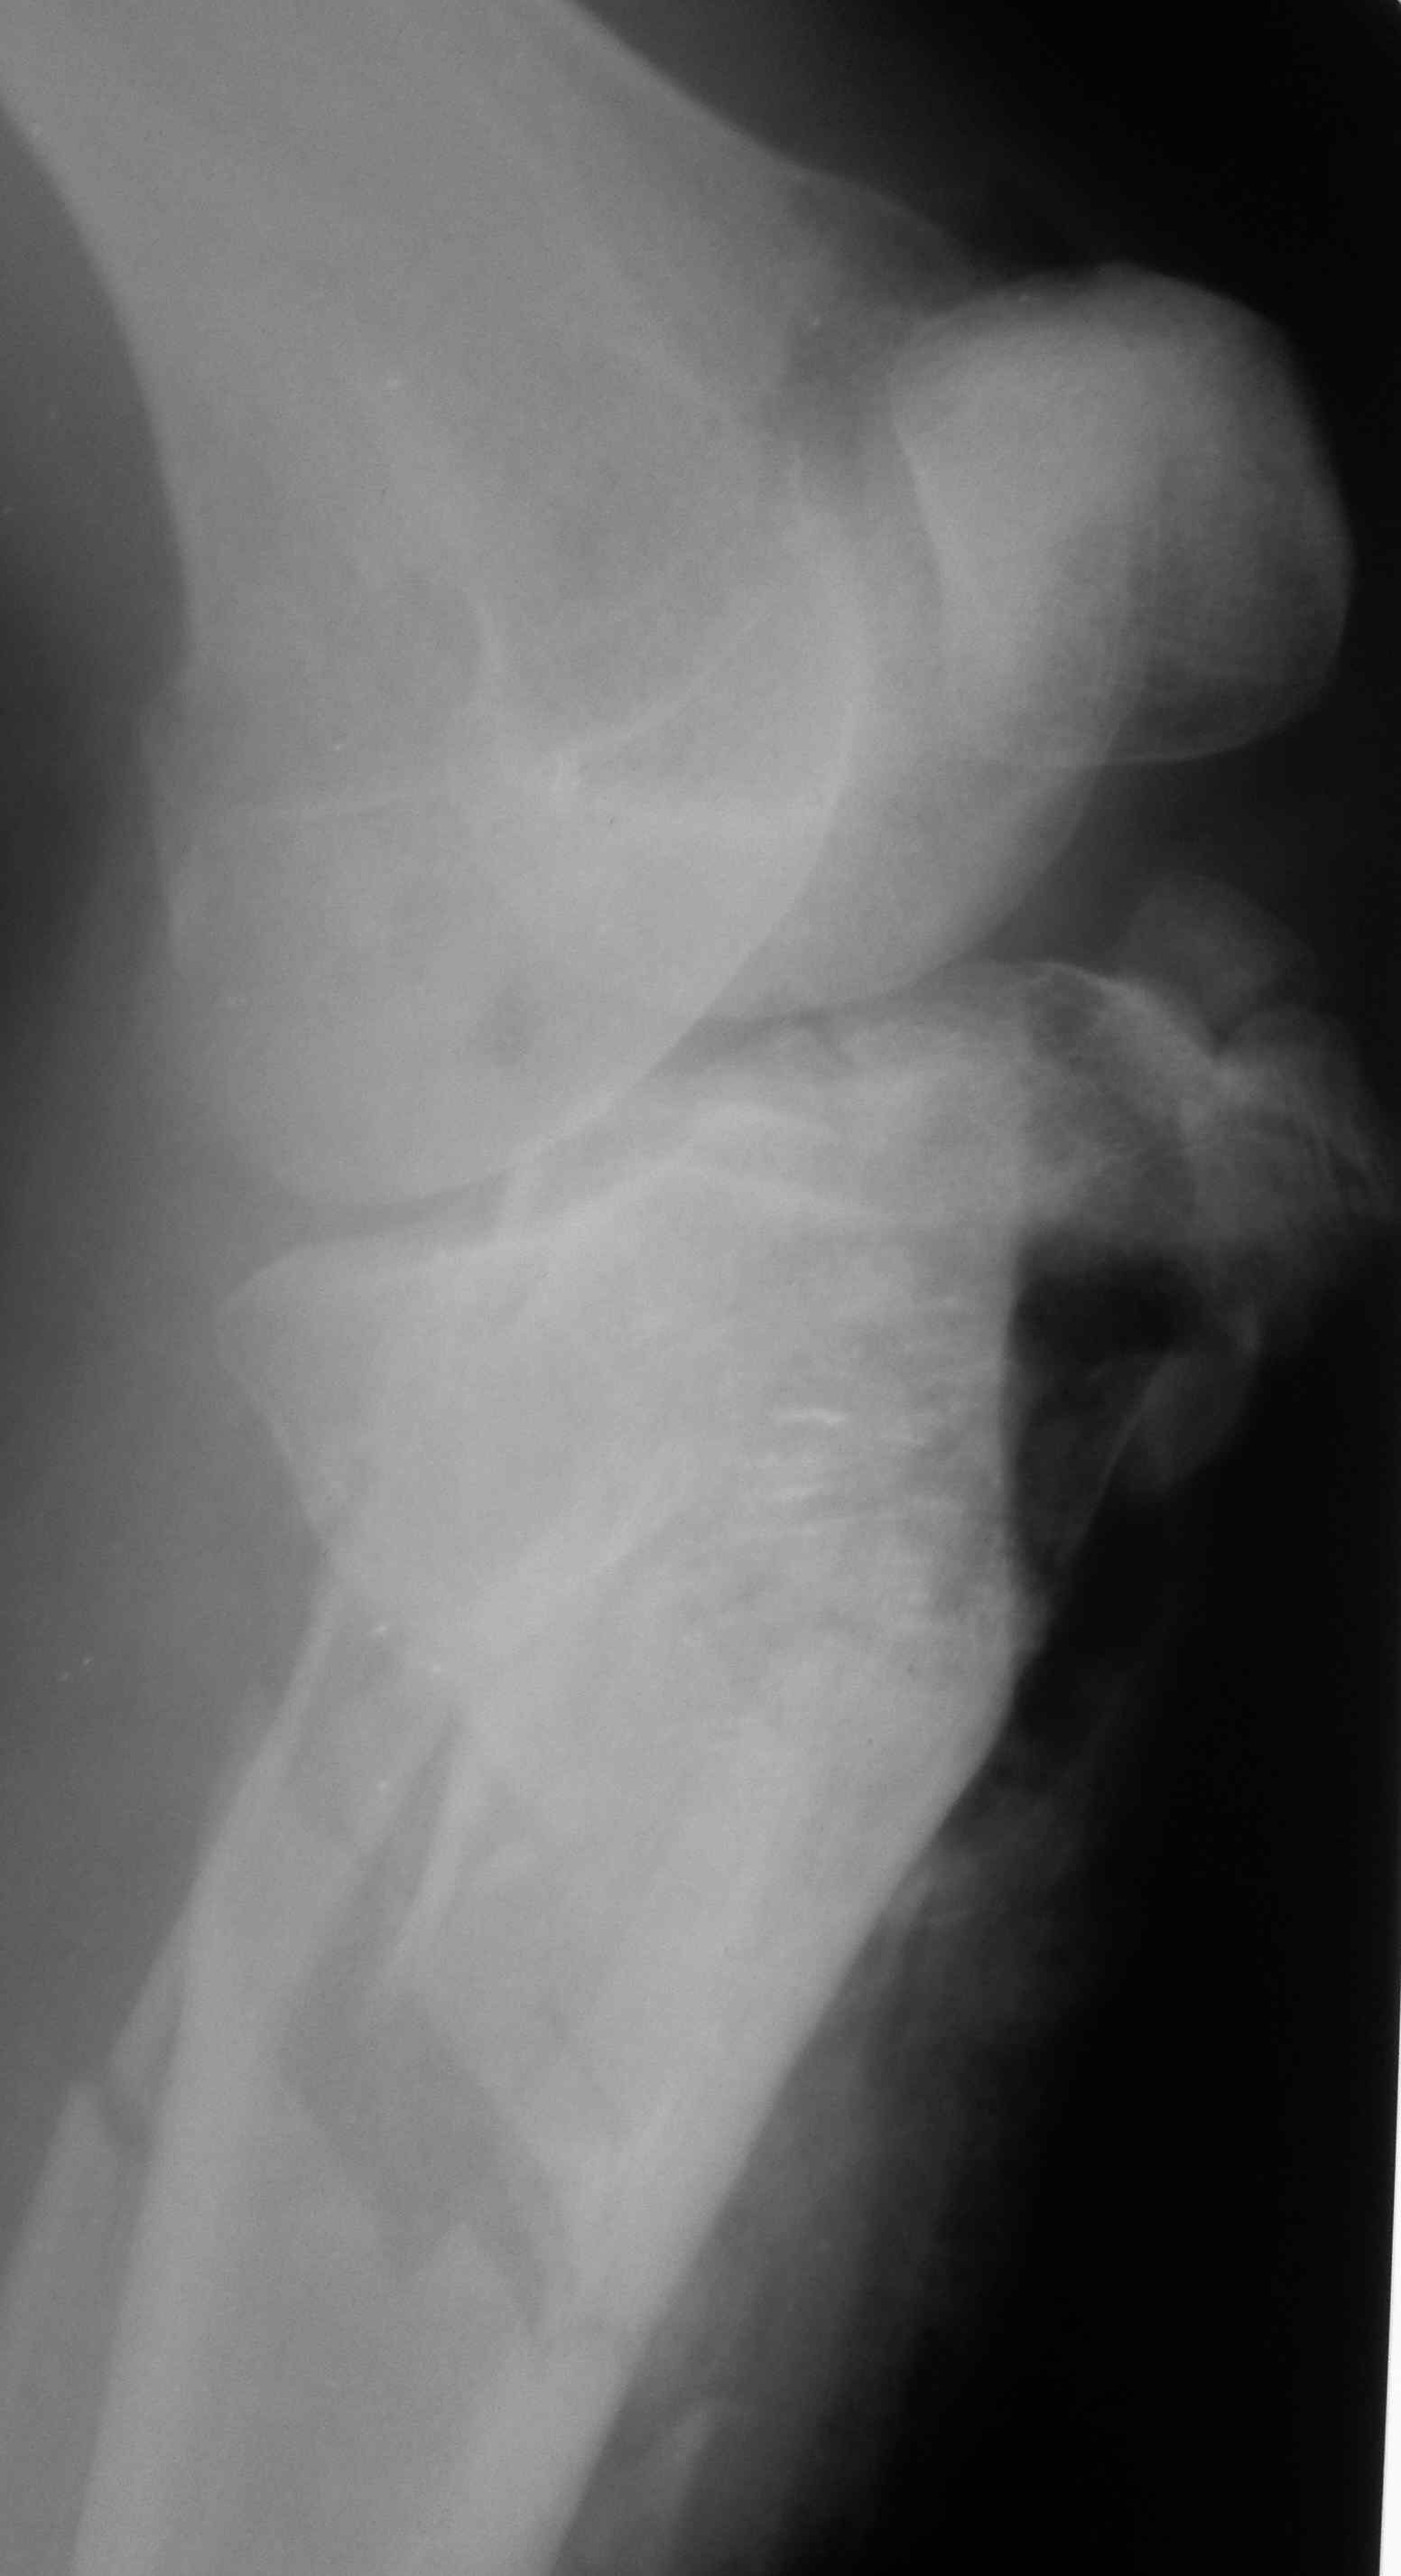

Перелом гиперэргический (тибия), в основном, метадиафизарный, без значимой импрессии (6 тип по Schatzker), то есть плато, как таковое, собрать будет не так сложно. Медиальный мыщелок цел и не импрессирован, а наружный сломан значительно сложнее. Если делать доступ, то латеральный и собирать наружный мыщелок к внутреннему. Другое дело, что если пойти на погружной синтез, то велик риск инфекционно-воспалительных осложнений (так как изначально перелом открытый). Мне думается, попытаться собрать плато закрыто под эопом (сдавить тазовыми шипцами мыщелки в медиалатеральном направлении и провести два-три стягивающих винта субхондрально), после чего смонтировать шарнирный АВФ с дистальной опорой на бедре и в этом же АВФ попытаться "поймать" бугристость ББК или зафиксировать ее отдельным винтом с шайбой.

скан, который, на мой взгляд наиболее интересен

Голень-41-С3.1 - полный внутрисуставной и метафизарный оскольчатый перелом с доминантным повреждением наружного мыщелка, с импрессией центральной части плато. Первичная тактика полный респект по АО и ОТА. на фоне лигаметотаксиса выполнено КТ, которое четко детализирует повреждение и определяет дальнейшую тактику.

Основная проблема не бугристость, а внутрисуставное повреждение латерального мыщелка с импрессией центральной части. С большей вероятностью, есть паракапсуллярное продольное повреждение наружного мениска.